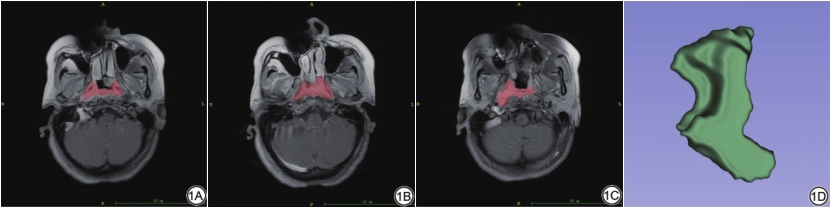

6名具有5~10年头颈部MRI诊断经验的影像科医生在3.6版本ITK-SNAP软件(www.itksnap.org)中,对患者3个序列的MRI图像沿肿瘤边缘逐层进行感兴趣区(region of interest, ROI)勾画,并由高年资医生进行核对,如不合格则重新勾画(图1)。所有图像中的注释信息在勾画前已被全部移除,所有勾画医生在勾画全程不知患者临床信息、治疗方式、临床结局及病理资料。勾画结果以原始图(nii)和感兴趣区(nrrd)格式保存。